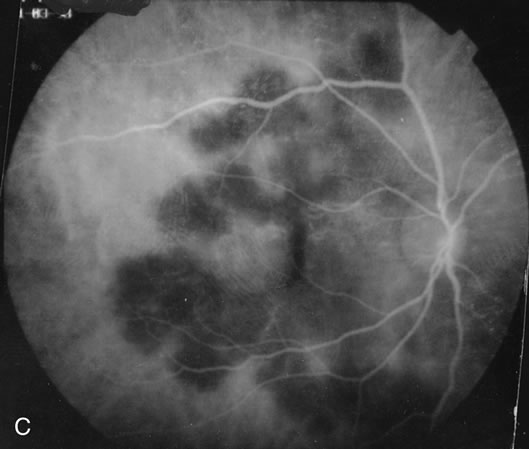

The chorioretinal lesions seen in PIC tend to be small and acutely no larger than 500 μm. They are yellow-whitish and they become atrophic punched out scars. The lesions can also coalesce. Approximately 40% develop choroidal neovascular membranes.40 Fluorescein angiography shows early hyperfluorescence with mild leakage in the later phases.65 There may be increased leakage at the edge in cases of choroidal neovascularization. ICG angiography shows hypofluorescence in the area of the lesions.66 Occasionally there may be some hyperfluorescent spots as well (Figs. 14 and 15).

Fig. 14. A. Right fundus photograph in a patient with multifocal choroiditis showing the small patches of choroiditis. Many have coalesced to form a larger patch. B. Left fundus photograph showing less involvement. C. Indocyanine green angiogram of the fundus shown in Figure 14a showing multiple hypofluorescent spots.

Fig. 15. A. Right fundus photograph of a patient with punctate inner choroidopathy showing the presence of a choroidal neovascular membrane. B. Fluorescein angiogram of the right eye demonstrating the presence of the choroidal neovascular membrane and perpipapillary window defect. C. Left fundus photograph showing large coalesced spots of inactive choroiditis. D. Fluorescein angiogram of the left eye showing staining of the areas of inactive choroiditis. Note the small areas of fluorescence that could not be seen by color photography.